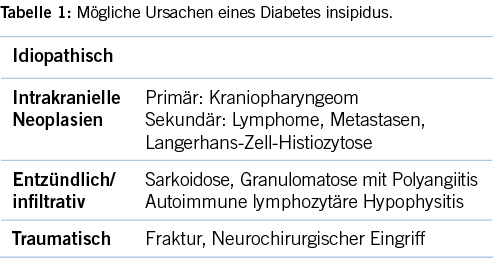

Im Gegensatz zu den Knochenschmerzen ist ein zentraler Diabetes insipidus, respektive ein Panhypopituitarismus sowohl bei Kindern als auch bei Erwachsenen ein sehr seltenes Krankheitsbild. Die häufigste Ursache des zentralen Diabetes insipidus ist idiopathisch. Bekannte Auslöser sind primäre Tumore (meist Kraniopharyngeom) oder sekundäre intrakranielle Neoplasien (Metastasen, Lymphome, Langerhans-Zell-Histiozytose (LCH)), infiltrative oder entzündliche Erkrankungen (Sarkoidose, Granulomatose mit Polyangiitis, autoimmune lymphozytäre Hypophysitis) oder traumatische Ursachen (Fraktur, neurochirurgischer Eingriff) [1] (Tabelle1). Bei allen Formen können magnetresonanztomographisch unspezifische Veränderungen (Verdickung des Hypophysenstiels, gesteigerte Kontrastmittel-Anreicherung) auftreten, so dass die bildmorphologischen Veränderungen bezüglich der Diagnosefindung oft nicht weiterhelfen. Aufgrund der Lokalisation ist die Abklärung mittels Gewebeuntersuchung eingeschränkt und oft nicht vertretbar.